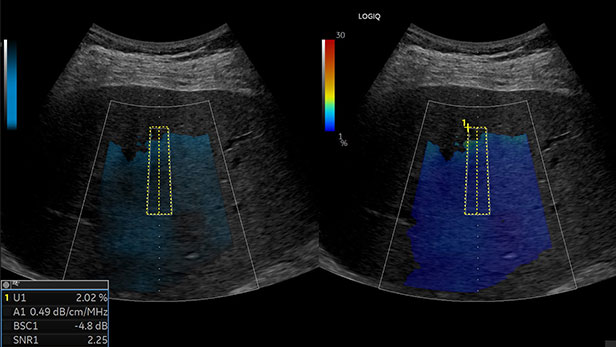

UGFF : LOGIQ franchit un cap dans la quantification

Avec l’introduction du mode UGFF (Ultrasound Guided Fat Fraction), le nouveau LOGIQ ne se contente plus de produire des images de qualité, il quantifie le pourcentage d'infiltration graisseuse !

Cette innovation marque une avancée majeure dans l’évaluation de la stéatose hépatique car elle est une des seules à utiliser une technologie basée sur 3 paramètres pour plus de précision et de robustesse :

• Mesure quantitative, non invasive et rapide de la fraction graisseuse

• Détection améliorée des stades précoces (S1, S2) et avancés (S3)

• Contribution à une prise en charge plus précoce et personnalisée

• Dans un contexte d’augmentation des pathologies métaboliques, UGFF positionne

L’échographie comme une alternative robuste et accessible aux techniques plus lourdes, tout en apportant une valeur clinique significative.